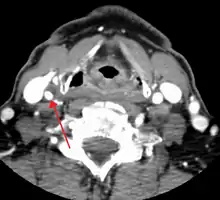

Carotid artery stenosis is usually diagnosed by color flow duplex ultrasound scan of the carotid arteries in the neck. This involves no radiation, no needles and no contrast agents that may cause allergic reactions. This test has good sensitivity and specificity.[16]

One of several different imaging modalities, such as a computed tomography angiogram (CTA)[18][19][20] or magnetic resonance angiogram (MRA) may be useful. Each imaging modality has its advantages and disadvantages - Magnetic resonance angiography and CT angiography with contrast is contraindicated in patients with chronic kidney disease, catheter angiography has a 0.5% to 1.0% risk of stroke, MI, arterial injury or retroperitoneal bleeding. The investigation chosen will depend on the clinical question and the imaging expertise, experience and equipment available.[21]